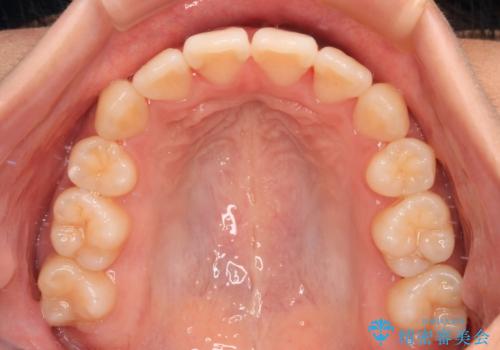

舌の突出癖が認められると、上下前歯の隙間を閉じることができません。

舌のトレーニングをしっかりと行っていただくことで、歯列を整えることができます。

- 矯正治療後の保定が不十分だと後戻り(元の位置に戻ろうとする動き)をします